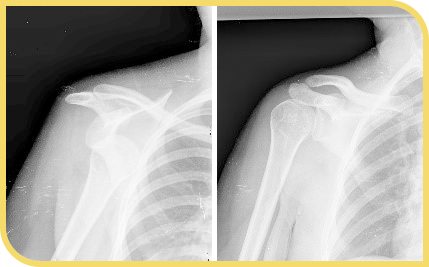

Las lesiones más típicas incluyen tendinitis del manguito rotador, luxación glenohumeral (hombro), luxación acromioclavicular y fracturas de clavícula. De estas lesiones, sólo las fracturas de húmero y de clavícula han aumentado en estudios epidemiológicos recientes, probablemente debido a la mayor velocidad que consiguen los deportistas gracias a los nuevos materiales.

Radiografía derecha: relación normal de los huesos tras la maniobra de reducción.

La mayor parte de estas lesiones suelen tratarse de forma aguda con la inmovilización del hombro en un cabestrillo. El tratamiento es urgente en la luxación glenohumeral que requiere de una reducción de la articulación. El conocimiento y atención del personal de pista ha mejorado mucho en los últimos años y suelen ser capaces de reconocer y reducir la lesión en pista.

Sin embargo, algunas de estas lesiones pueden producir una fractura asociada y es recomendable realizar pruebas radiológicas adicionales para identificar estas lesiones. La mayoría requieren de un tratamiento mediante inmovilización y rehabilitación posterior. Otras lesiones, sin embargo, terminarán necesitando de una intervención quirúrgica.